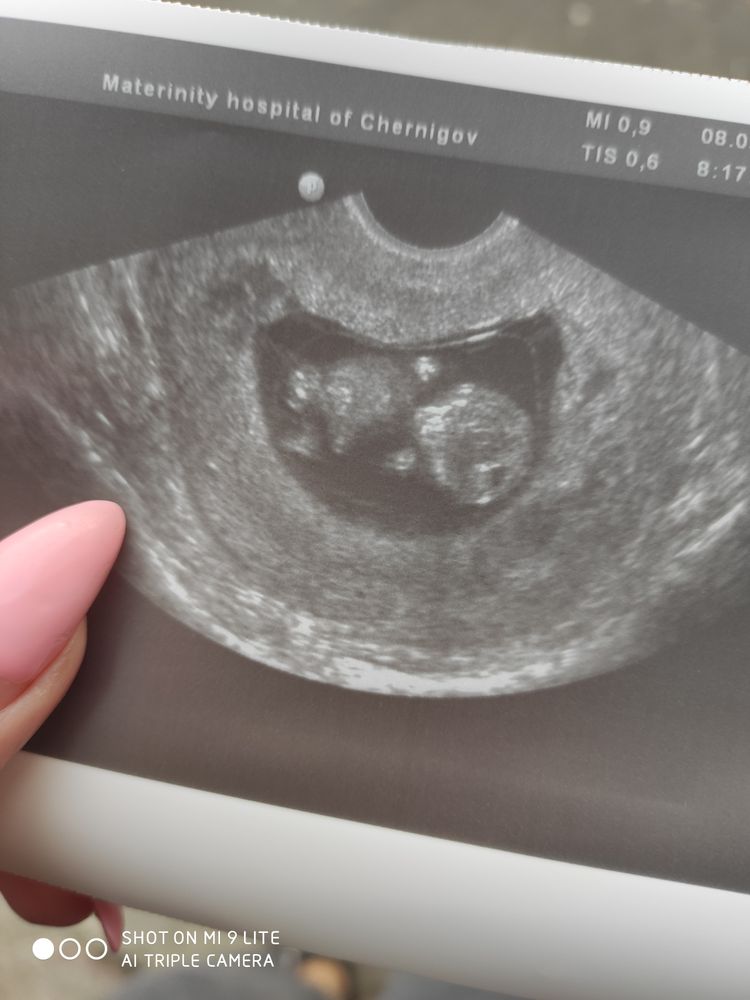

Всё о нашей беременностиТак как лежу в больнице скучно жесть,столько видео пересмотрела про малышиков,на каком сроке как выглядят,какие ощущения,через неделю на скрининг,надеюсь что будет все хорошо. Как кто себя чувствовал на 11 неделе?)))фото моей малявочки

Да , на таком сроке они уже ручками ножками шевелят, крутятся , ротик открывают, милота, жду не дождусь 1 скрининг 🙏🙏🙏